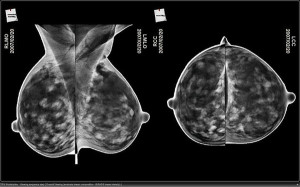

L’attuale mammografia a raggi X, bidimensionale e’ il sistema piu’ diffuso per l’individuazione del cancro alla mammella nelle donne ma ha qualche limite. Per esempio, il tessuto sano circostante puo’ mascherare una lesione che, se e quando individuata, non e’ mai stimata volumetricamente. La nuova tecnica oggetto della ricerca si chiama mammografia digitale stereoscopica e attraverso un’immagine 3D riesce a superare queste limitazioni. Questa impiega sempre la tecnologia della mammografia digitale in 2d ma i raggi X sono modificati in modo da muoversi separatamente e creare due differenti prospettive che danno l’illusione della visione tridimensionale. “Nella nostra tecnica i canali dei raggi X funzionano come gli occhi, con due differenti immagini che forniscono differenti viste della struttura interna della mammella”, ha spiegato Carl D’Orsi, fra gli autori della ricerca. In un test condotto su 779 pazienti a elevato rischio di cancro, l’accuratezza dell’individuazione del tumore e’ risultata migliore nel caso della tecnica 3d: 90,9 per cento contro l’87,4 della mammografia bidimensionale, un aumento statisticamente significativo .